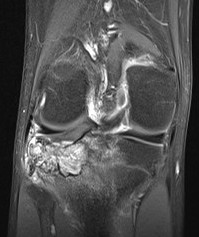

MRI

Rarely diagnostic

- high signal intensity on T2